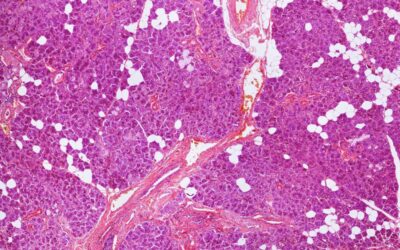

Saliva is an essential fluid for maintaining your oral health. What is it and how is it made? Saliva is secreted by the salivary glands (a microscopic view is shown) in your mouth and throat. The primary glands are called the parotid, submandibular, and sublingual...